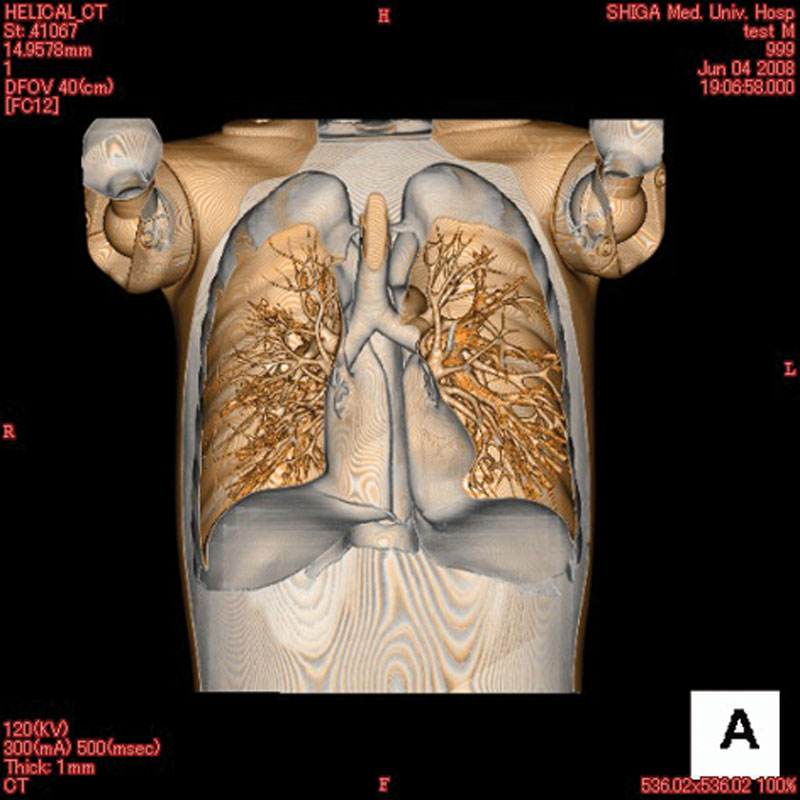

Ein einzigartiges Ganzkörperphantom für CT bietet eine Vielzahl von Ausbildungs- und Forschungsmöglichkeiten. Das Phantom kann auch für normales Röntgen benutzt werden und gibt lebensnahe Bilder. Es benden sich keine Metallteile oder Flüssigkeiten im Phantom. Die wichtigen Gelenke haben eine menschenähnliche Beweglichkeit und erlauben vielfältige Positionen für die Übung. Das Phantom kann in 10 Teile zerlegt werden. Die verbesserten Schultergelenke erlauben es, die Arme nach oben zu bewegen. Die künstlichen Organe sind anatomisch korrekt und haben entsprechende HU-Zahlen.

- Lungen mit Pulmonalgefäßen

- Luftröhre

Radiologische Absorption und Hounsfield-Nummer ähnlich dem menschlichen Körper.